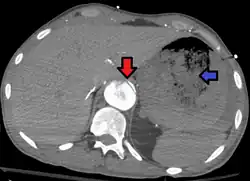

Aorto enteric fistula and aortic dissection of the thoracic aorta. Arrow shows the flap in the aorta. Heterogeneity is blood in the stomach |

An aortoenteric fistula is a connection between the aorta and the intestines, stomach, or esophageus.[1] There can be significant blood loss into the intestines resulting in bloody stool and death.[1] It is usually secondary to an abdominal aortic aneurysm repair. The third or fourth portion of the duodenum is the most common site for aortoenteric fistulas, followed by the jejunum and ileum.[2]

Diagnosis is typically via a CT angiography, esophagogastroduodenoscopy, or arteriography.[1] It is part of the differential diagnosis of gastrointestinal bleeding.[2]